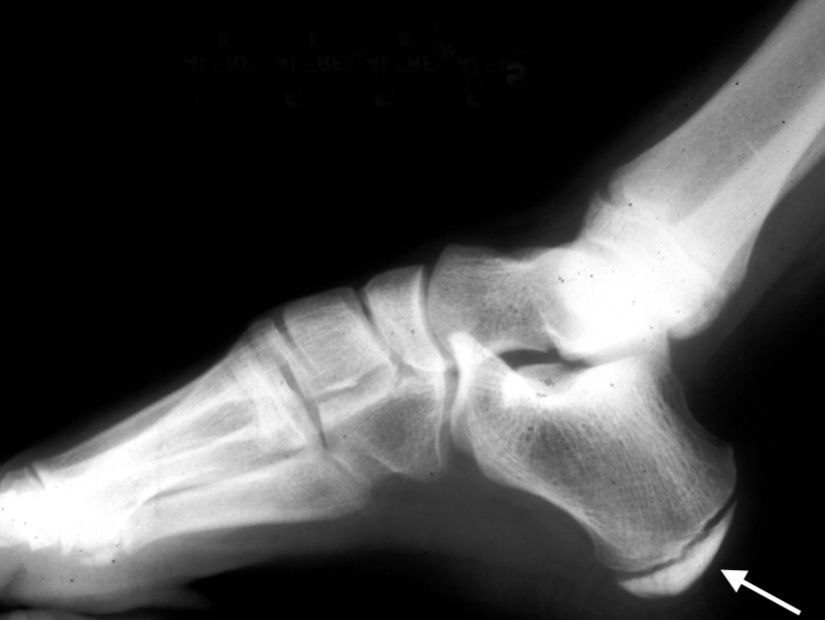

Sever's disease affects the part of the growth plate at the back of the heel. This growth area serves as the attachment point for the Achilles tendon — the strong band of tissue that connects the calf muscles at the back of the leg to the heel bone.